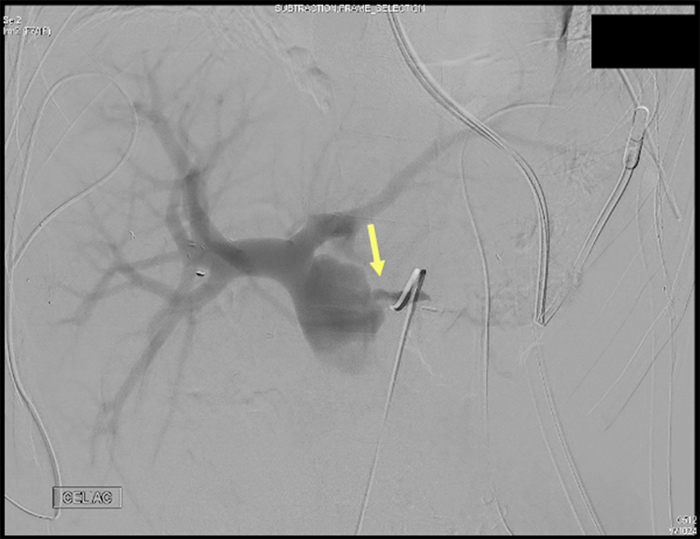

The patient was a 24 year-old-male who sustained a gunshot wound to his right flank. On arrival, the patient was hemodynamically unstable and taken to the operating room. Massive hemoperitoneum was immediately encountered. A complex liver laceration was identified involving segments four, five, and eight. A lateral portal vein injury was found and primarily repaired. The hepatic arteries were examined, and no injuries were identified. The hepatic injury was packed. The patient also had a distal transverse colon injury which required segmental resection. Due to the bullet trajectory, the lesser sac was opened, which revealed a distal pancreatic contusion that was packed. Due to hemodynamic instability, the patient was left in discontinuity, and a temporary abdominal closure system was applied. Once stabilized in the intensive care unit, a CT with IV contrast was obtained that demonstrated a traumatic arteriovenous fistula between the common portal vein and left hepatic artery (Figure 1) as well as a grade III laceration of the distal pancreas. The patient was taken back for re-exploration where he underwent distal pancreatectomy, splenectomy, colo-colonic anastomosis, and replacement of temporary abdominal closure system.

Figure 1. Arterioportal Fistula Involving Left Hepatic Artery and Main Portal Vein: A) Coronal and B) Axial. Published with Permission